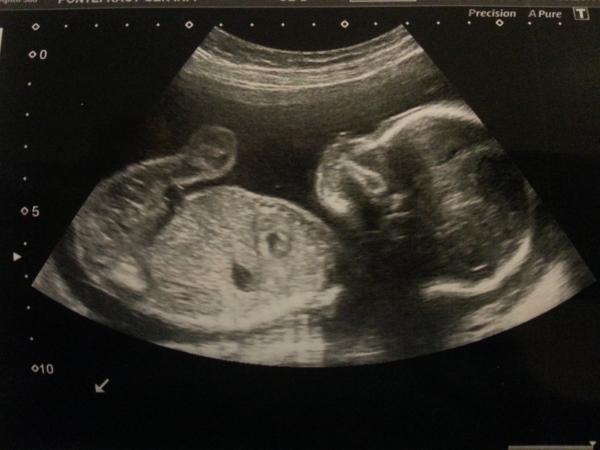

Just wanted to say a massive thanks for wishes of luck before the scan. It really helped - especially as I was so nervous beforehand that I was sick! It all went well though and we are now Team Pink! The sonographer said they'd only seen boys for the past couple of days as well, which was interesting.

kicksandgiggles EDD 8th September (but 18th August is term for twins) Team Blue